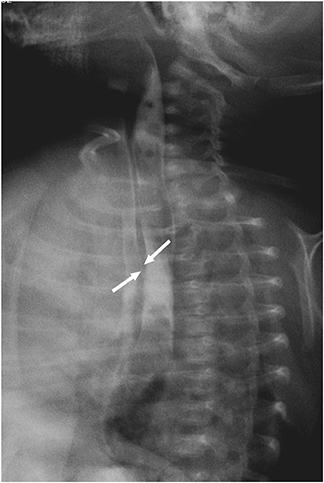

Fig. 1). Upper gastrointestinal (GI) series showed gastroesophageal regurgitation with pulmonary aspiration but esophagoscopy and video esophagogram on the eleventh day of life showed no abnormality. Contrast esophagogram was followed on the 33

rd day of life, and an H-type TEF was found at 1 cm above the carina, at T4 level (

Fig. 2). Surgical repair was performed on the 37

th day of life through a right posterolateral thoracotomy incision. The fistula was positively identified, divided, and closed with non-absorbable interrupted sutures during the operation.

Fig. 2 H-type tracheoesophageal fistula at 1 cm above the carina (white arrows).